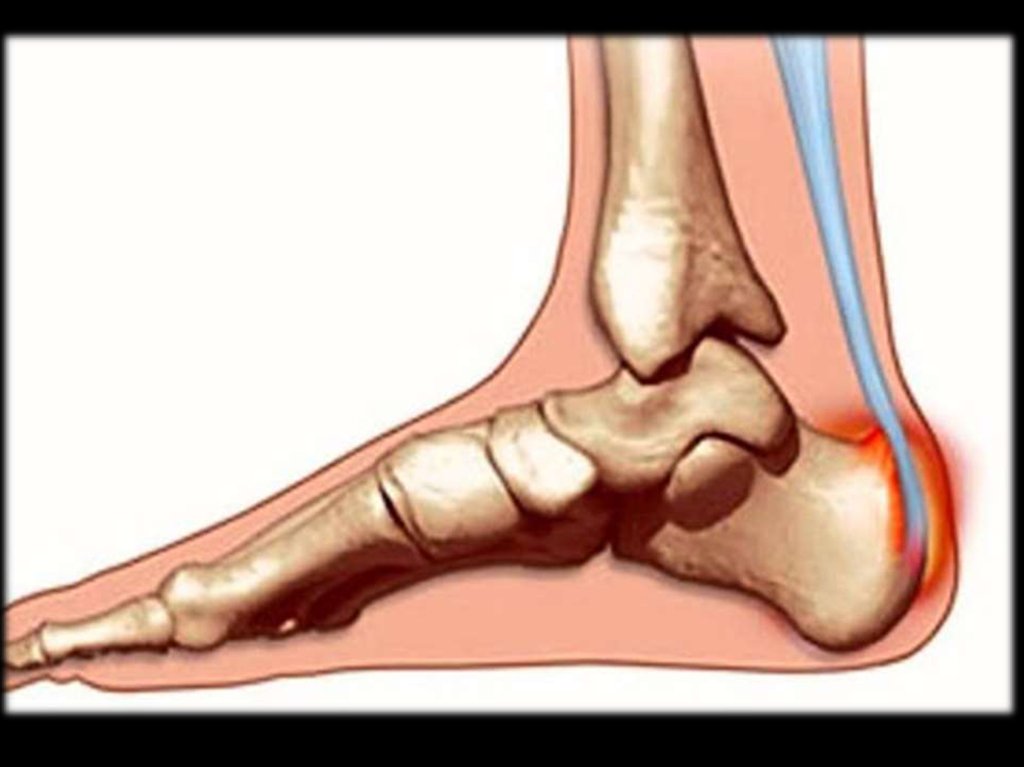

51. Тендинит ахиллового сухожилия

53. Подкожный бурсит ахиллового сухожилия